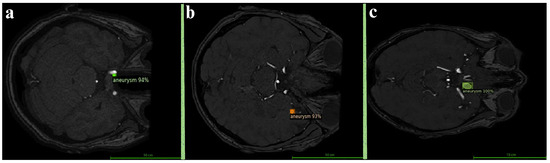

Magnetic resonance imaging (MRI) is a medical imaging technique used in radiology to generate pictures of the anatomy and the physiological processes inside the body. MRI scanners use strong magnetic fields, magnetic field gradients, and radio waves to form images of the organs in the body. The technology continually evolves as groundbreaking innovations and applications emerge. For example, some researchers use non-contrast MRI surveillance of craniopharyngiomas; some researchers found that by employing the spherical mean MRI technique, they can detect the IDH status in brain gliomas; and some researchers utilize generative artificial intelligence to transform grayscale MRI images into colour. This helps us to better understand multiple sclerosis, among other diseases.